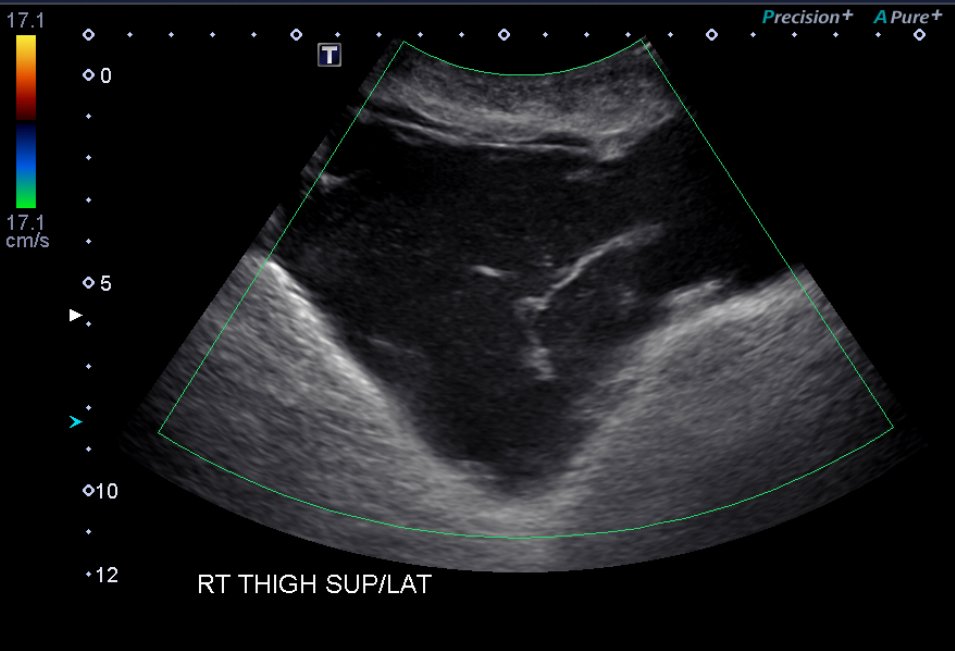

On physical examination, he was noted to have a nearly “watermelon-sized” fluctuant mass to his right lateral superior quadriceps with multiple overlying abrasions (Image 1). Computed tomography (CT) scans of the area showed a large heterogeneous collection measuring roughly 37×9.5×16 centimeters in the subcutaneous adipose layer of the lateral right thigh (Image 2), while ultrasonography revealed a complex fluid collection containing some nodular solid components and debris (Image 3). Additionally, radiographs confirmed multiple fractures including most significantly a pelvic ring fracture. Surgical debridement, evacuation, and sclerodhesis were performed nine weeks post injury to allow overlying abrasions to heal prior to intervention.